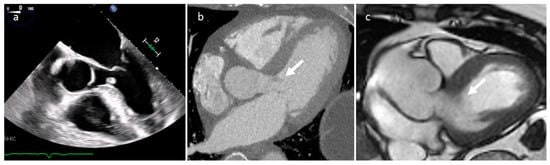

3.5. Coronary Artery Aneurism (CAA)

| Coronary artery aneurisms | Adulthood | AV groove | Asymptomatic | Vascular mass | AV groove mass | Dilatation, thrombus, fistula | Vascular enhancement |